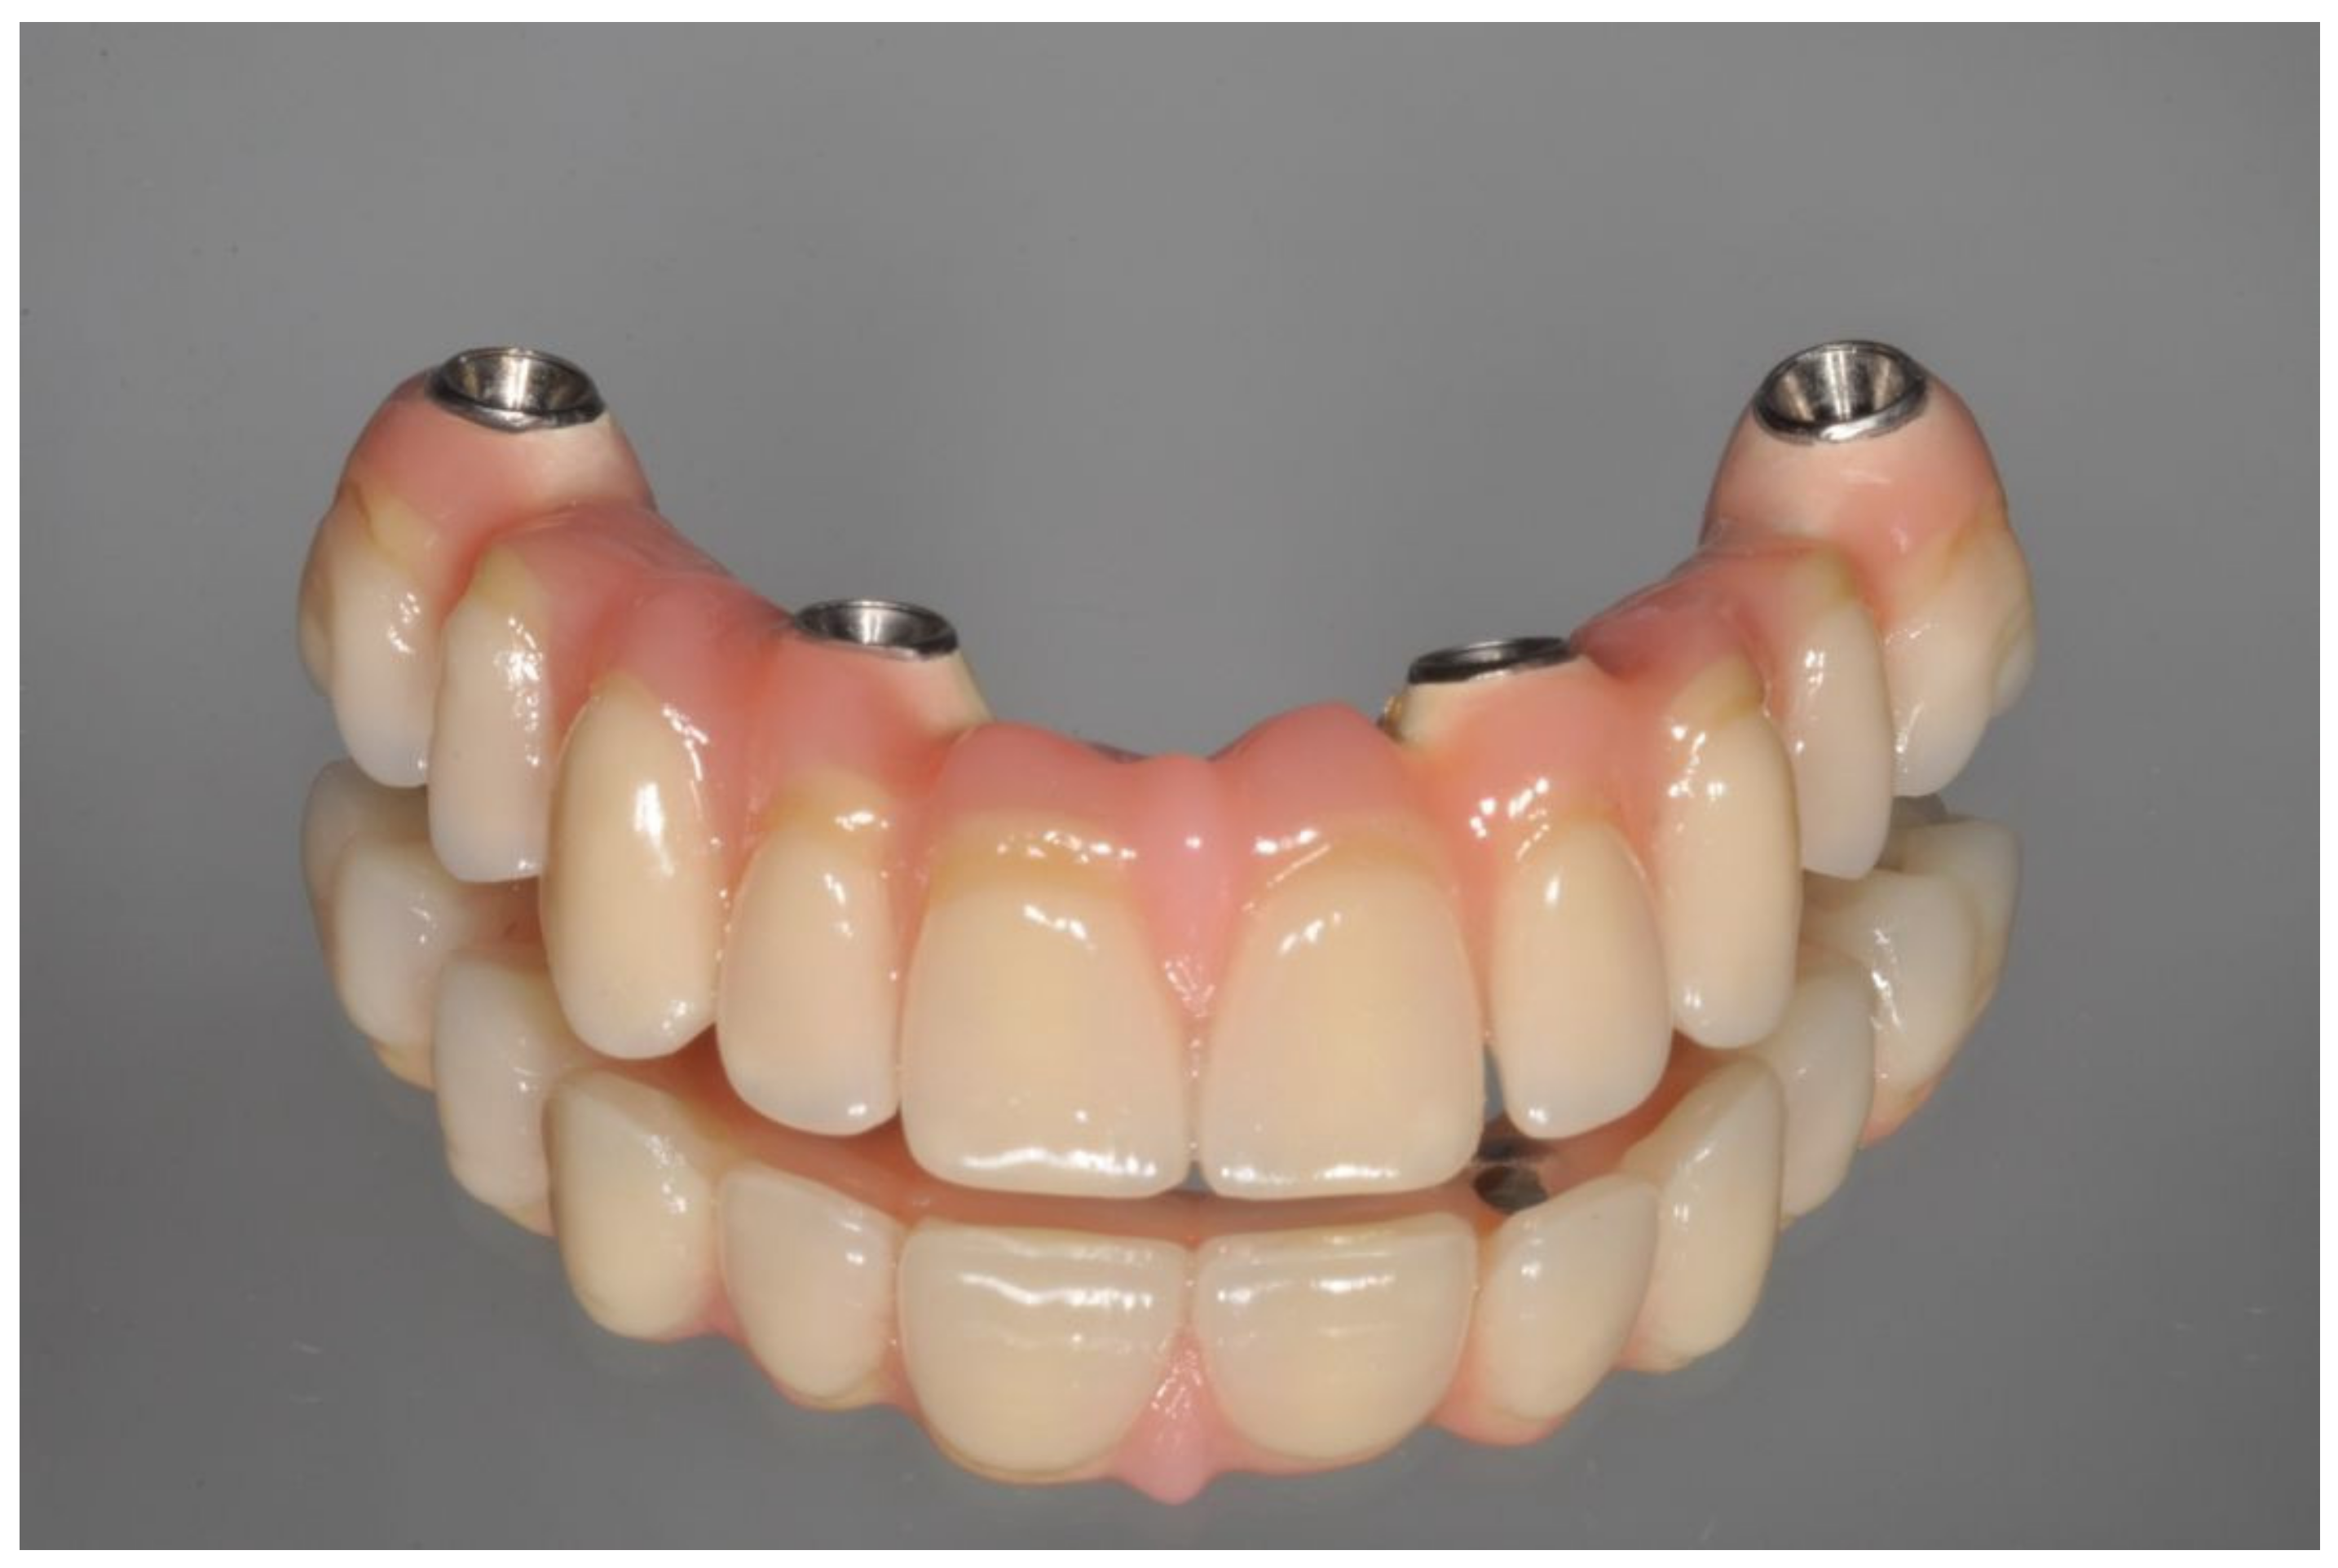

Figure 6.

Definitive prosthesis with cantilevers after 7 years of use.

Figure 7.

Occlusal view of definitive prosthesis after 7 years of use.